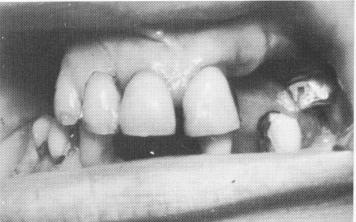

Fig. 15-70. The remaining upper teeth are seen. The alveolar bone in the right posterior quadrant was completely resorbed buccolingually to such an extent that the original ridge crest was so far lingual to the lower ridge that the upper teeth were completely lingual to the lower ones, with no contact.

The patient had five remaining maxillary teeth—the left central incisor, the left second molar, and the right central, lateral, and cuspid teeth (Fig. 15-70). Furthermore, her right maxillary ridge was practically nonexistent; if teeth were constructed to